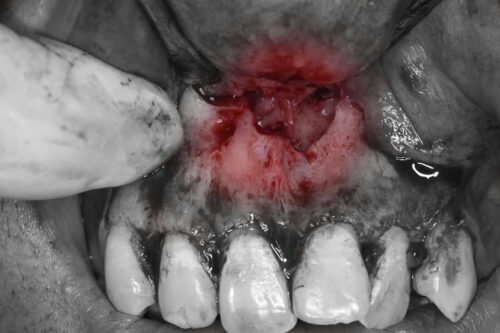

Trong nha khoa, các trường hợp răng thừa ngầm, đặc biệt là ở vùng cửa, là vấn đề không hiếm gặp. Răng thừa ngầm là những chiếc răng không hoàn chỉnh, mọc lệch, hoặc nằm dưới nướu mà không thể tự trồi lên bề mặt. Các răng này có thể gây ra nhiều vấn đề cho bệnh nhân như viêm nhiễm, nhiễm trùng, hoặc ảnh hưởng đến quá trình mọc của các răng khác. Phẫu thuật lấy răng thừa ngầm vùng cửa là một phương pháp điều trị phổ biến để giải quyết tình trạng này. Bài viết này sẽ trình bày chi tiết về quy trình, lý do, và các yếu tố cần lưu ý khi thực hiện phẫu thuật lấy răng thừa ngầm.

- Kích thích viêm nhiễm: Răng thừa ngầm có thể gây viêm nhiễm trong mô lợi hoặc mô xương xung quanh. Điều này có thể dẫn đến các triệu chứng như đau, sưng, và khó chịu.

- Tổn thương mô xương: Các răng thừa ngầm lâu ngày có thể tạo ra một lực không đều lên xương hàm, dẫn đến tổn thương hoặc tiêu xương.